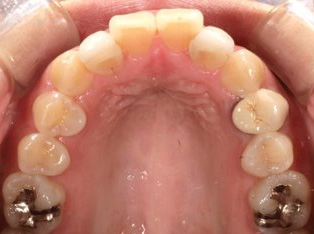

治療前

治療終了前